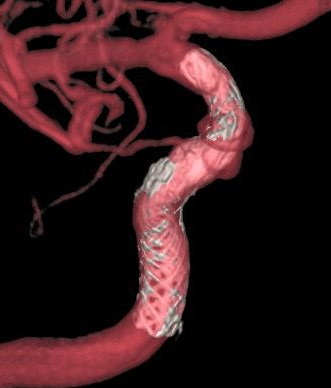

4mm×30mm Streamline

术后4月余随访:多发动脉瘤均未见显影,远端残余轻度狭窄

术前术后对比